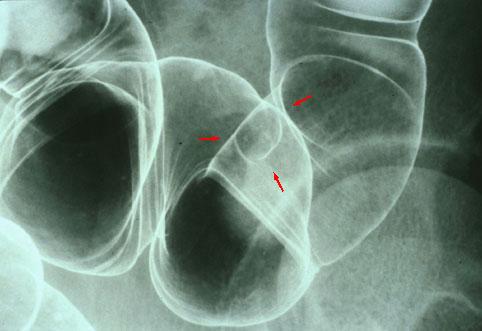

Linfangioma del Sigmoides que se describió por Rayos X, endoscopía, ecografía, TAC, Colonoscopía por CAT (Presentado por el Dr. Kawamoto de la Sociedad Gastrointestinal de la Universidad de Kyushu)

Tumor no Epitelial Benigno/Linfangioma

colon/sigmoides

Rayos X

10 - 14